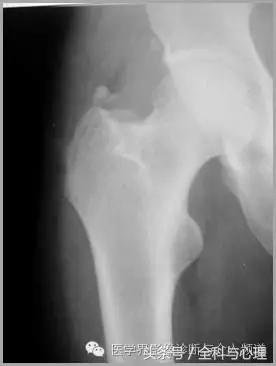

软组织钙化与骨化,软组织钙化和骨质增生 大粗隆滑囊炎

软组织钙化与骨化,软组织钙化和骨质增生